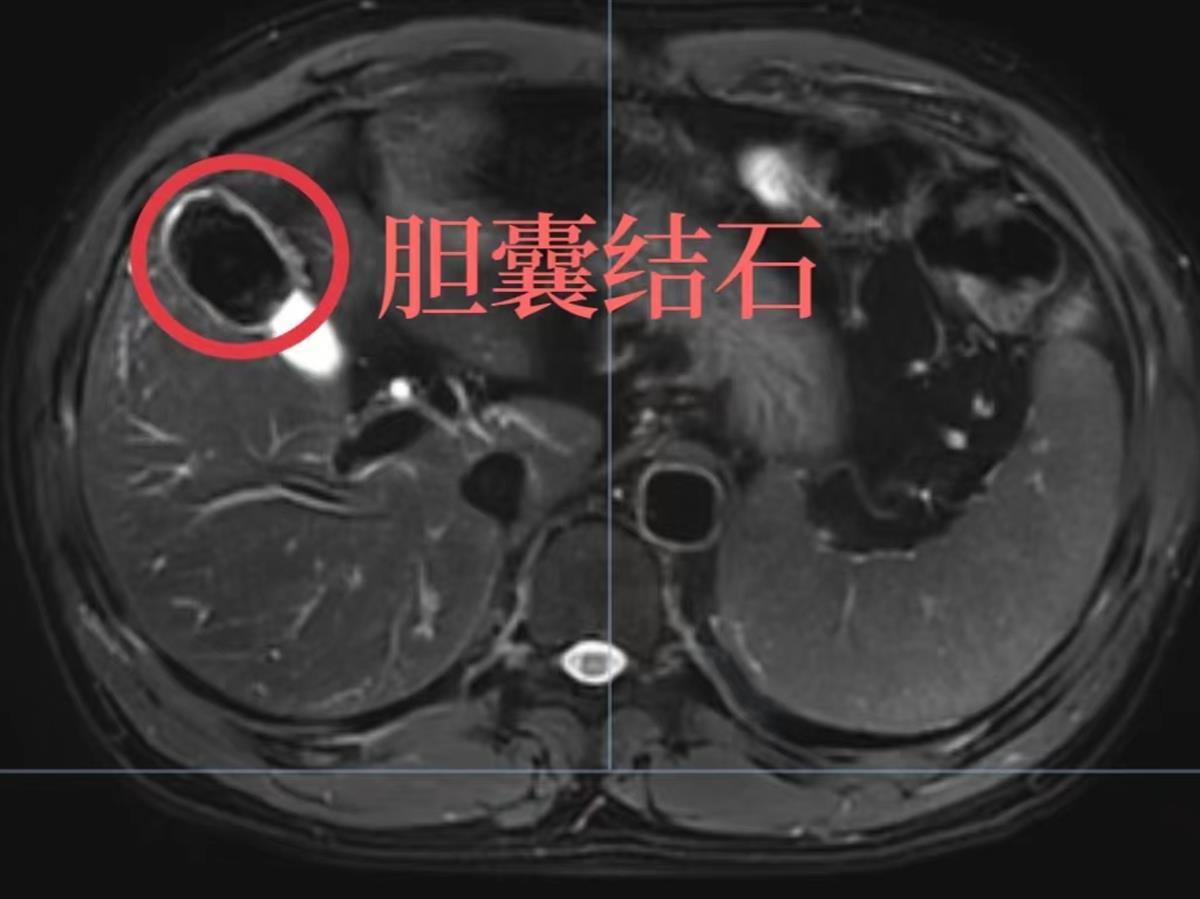

从磁共振可以清晰地看到徐大哥的胆囊结石

结合两人的相关检查结果,团队进行了术前评估。从已有的检查结果看,大哥属于慢性胆囊炎,只有一颗完整的结石,而徐先生则是急性化脓性胆囊炎,炎症非常重,且是填满型胆囊结石,胆囊颈部还有一颗直径约1.5厘米的结石嵌顿。